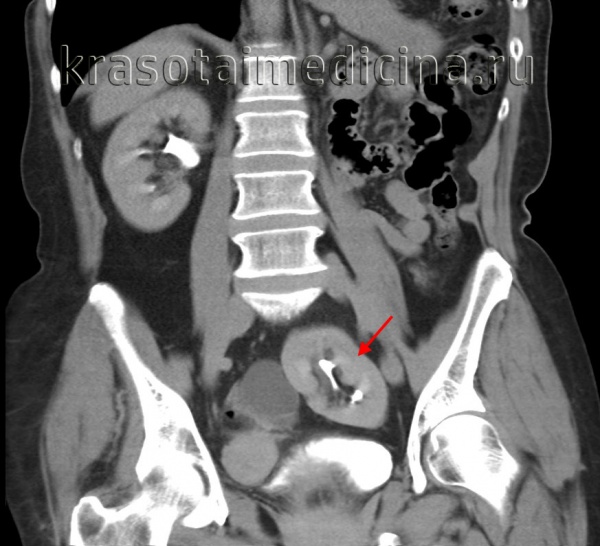

3. КТ при подковообразной почке:

• КТ с контрастированием:

о Позволяет определить структурные аномалии:

- Степень и локализация сращения: срединное или боковое сращение

- Степень мальротации почки

- Изменения почечной паренхимы (например, рубцевание, поликистоз)

- Аномалии собирательной системы (например, удвоение системы, гидронефроз)

о Позволяет дифференцировать структуру перешейка (фиброзная или нормальная паренхима)

- КТ почти всегда позволяет визуализировать функционирующую паренхиму в перешейке

(Слева) КТ с контрастированием, аксиальная проекция, отсроченный снимок: подковообразная почка с расширенными чашечками с левой стороны. Множественные почечные артерии пересекают перешеек и почечную лоханку, что может способствовать обструкции.

(Справа) КТ с контрастированием, объемная реконструкция в коронарной плоскости: у этого же пациента визуализированы множественные почечные артерии некоторые из которых, вероятно, пересекают и частично перекрывают лоханку на левой стороне. Чашечки с левой стороны расширены, а также истончено корковое вещество.